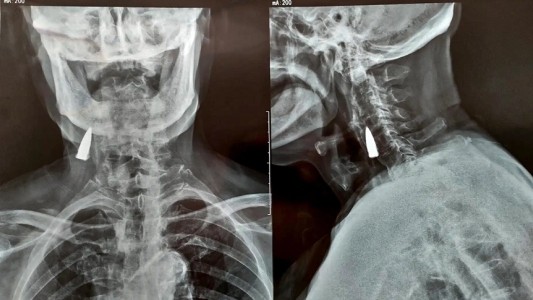

Tras sufrir una caída en su balcón, fue al hospital y descubrieron que tenía una bala en el cuello